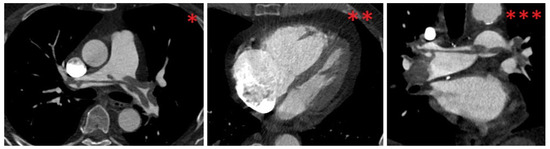

The ECG revealed sinus tachycardia (116 bpm), an SIQIII type, an incomplete right bundle branch block (RBBB, QRS time: 110 ms) and persistent S waves in leads V5 and V6. In addition, T wave inversions (TWI) were found in leads III, aVF and V1–V3. Moreover, a parameter for right heart strain (R V1, V2 + S I, aVL − S V1) exceeded a threshold of 0.6 mV (0.7 mV), and the time to peak of the R wave in V1 was longer than a threshold of 35 ms (60 ms) [18]. Due to the suspicion of PE, Wells I and Wells II scores were assessed, and the results (6/12.5 and 3/7, respectively) indicated likely PE [19,20]. Due to the patient’s hemodynamic stability, a computed tomography pulmonary angiogram (CTPA) was performed, in which a bilateral, central saddle PE and vivid signs of right heart strain (right ventricle-to-left ventricle diameter ratio: 2.2) were observed (Figure 2).

Figure 2. CTPA findings at time of diagnosis. * and **: axial view. ***: coronal view; bilateral, central saddle pulmonary embolism (*, ***); pulmonary artery-to-aorta diameter ratio > 1 (1.1, *); caval contrast reflux (**); D-sign (**); right ventricle-to-left ventricle diameter ratio > 1 (2.2, **); CTPA, computed tomographic pulmonary angiography.